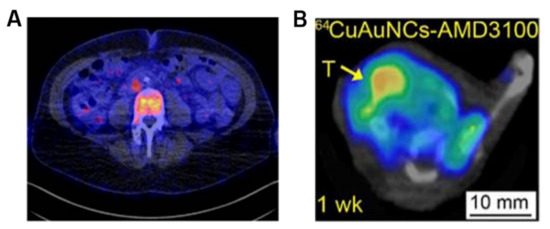

- Dijkers, E.C.; Oude Munnink, T.H.; Kosterink, J.G.; Brouwers, A.H.; Jager, P.L.; de Jong, J.R.; van Dongen, G.A.; Schröder, C.P.; Lub-de Hooge, M.N.; de Vries, E.G. Biodistribution of 89Zr-trastuzumab and PET Imaging of HER2-Positive Lesions in Patients With Metastatic Breast Cancer. Clin. Pharmacol. Ther. 2010, 87, 586–592. [Google Scholar] [CrossRef]

| HER2 | PET | Antibody | 89Zr-trastuzumab | 1. Radiolabeling efficiency: 77.6 ± 3.9% 2. Radiochemical purity: 98.1 ± 1.1% | 1. Low sensitivity 2. Liver and spleen had higher uptake | [15] | |